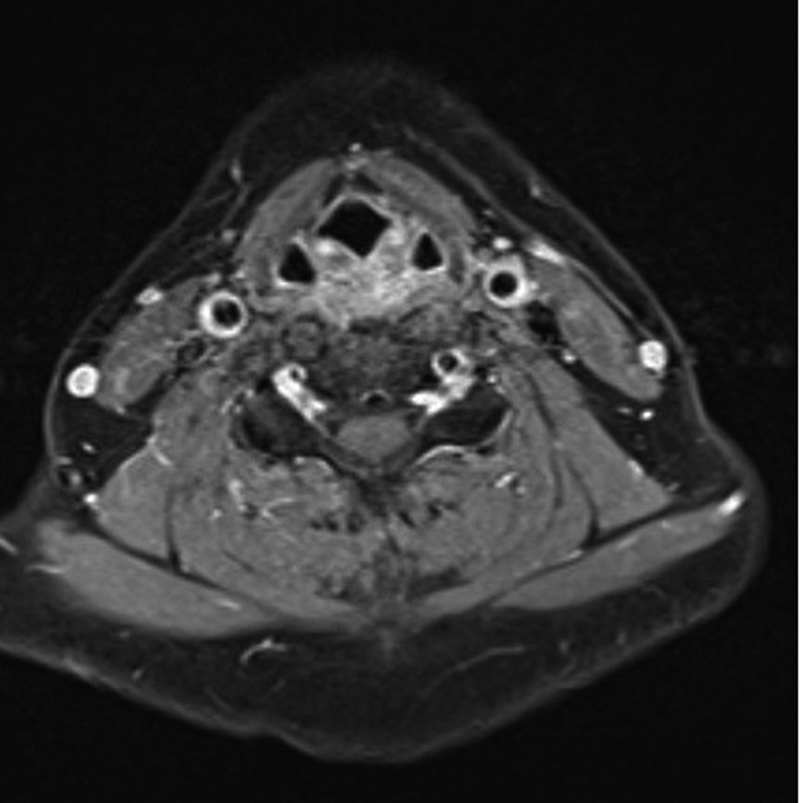

颈动脉短暂性血管周围炎(TIPIC)综合征,历史上曾被命名为特发性颈动脉炎或费氏综合征,是一种以颈动脉炎症和疼痛为特征的罕见疾病。诊断需要特殊的临床放射学表现。我们描述了一名 37 岁女性的病例,她出现头痛和左颈部疼痛,被诊断为伴有暂时性血管周围浸润的 TIPIC 综合征。

Transient perivascular inflammation of the carotid artery (TIPIC) syndrome, historically named idiopathic carotidynia or Fay syndrome, is a rare condition characterized by inflammation and pain in the carotid artery. The diagnosis requires a specific clinical-radiological presentation. We describe a 37-year-old female who presented with headaches and left neck pain and was diagnosed with TIPIC syndrome with temporary perivascular infiltration.